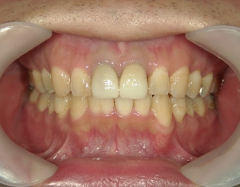

矯正歯科 治療前矯正歯科 治療前

33歳男性 浜松市東区在住

治療期間1年7ヶ月

主訴:前歯の歯並びが気になる。

矯正歯科 治療前 上顎の左右4番計2本を抜歯し叢生を改善。